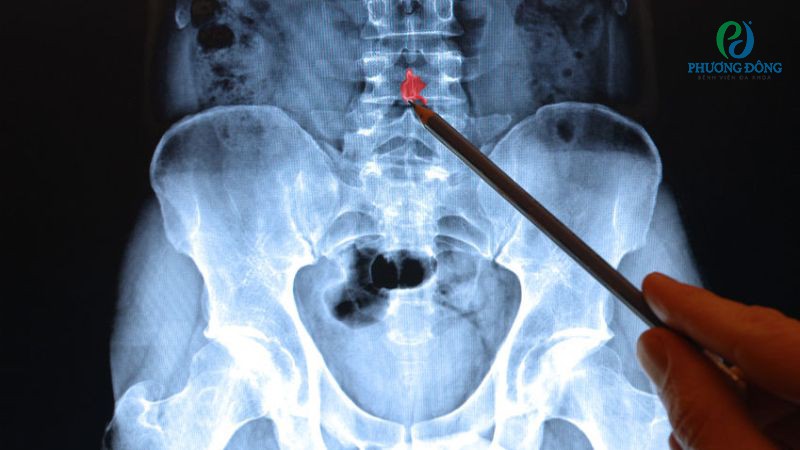

- Chụp X-quang: Xét nghiệm hình ảnh học phát hiện vị trí các gai xương, mức độ dây thần kinh bị chèn ép.

Phương pháp chẩn đoán xác định mức độ, vị trí gai xương